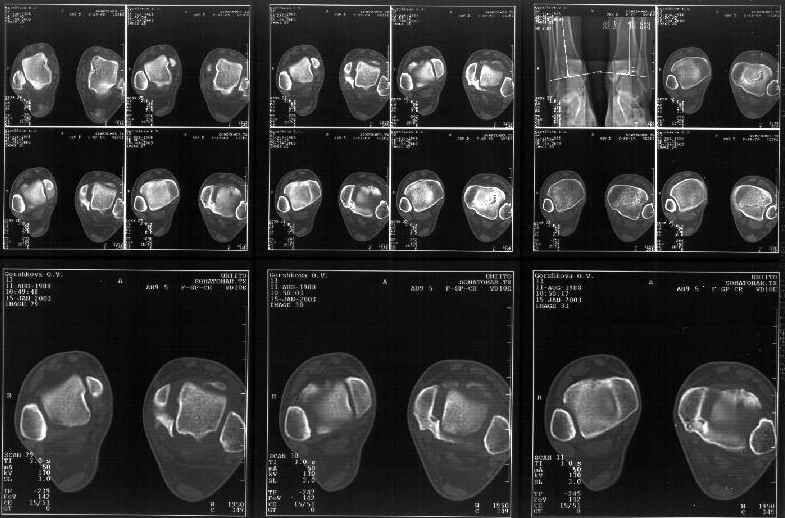

На следующий день пациентке сделали КТ. Может быть, после просмотра картинки будут другие предложения? Не убрать ли ве-таки этот фрагмент

позади внутренней лодыжки, который оттесняет таран кнаружи?

Думаю, КТ прочитан не верно. Задняя часть медиального маллеола, в сущности уже часть заднего маллеола стоит на месте и трогать её не следует. Передняя часть маллеола на 3-4 мм удалена от тарана. Сравните с пространством между

латеральным маллеолом и тараном. В норме все три должны быть одинаковы: между тараном и латеральным, задним и медиальным. Это главное условие устойчивого сидения тарана в голеностопном суставе.

Все-таки она как раз была была отколота и вместе с тараном смещена латерально.

Внутренняя лодыжка не была сломана, она как была на своем месте, так там и находится. Это таран от нее отдавлен кнаружи смщенным в его сторону фрагментом позади внутренней лодыжки. За счет чего и есть проявления нестабильности связок.

Мне в тоже время совершенно ясно видно по той же КТ, по 4 срезам, расположенным в центре и вверху пленки, что перелома внутренней лодыжки не было, в следующем собщении я приложу увеличенный фрагмент томограммы. А к этому письму прилагаю увеличеный фрагмент послеоперационной рентгенограммы, где выделил отколотый фрагмент

позади внутренней лодыжки. И он, как я вижу, находится между стержнем и тараном. А перелома внутренней лодыжки, и тем более смещения, IMHO

не определяется.

Здесь 4 среза, начиная от основания лодыжки и проксимальнее. Где, по Вашему мнению, проходит линия перелома, отделяющая переднюю часть внутренней лодыжки от большеберцовой кости? Заранее спасибо.

Я пометил линию перелома черной линией.

К сожалению на последних присланных срезах КТ нет более низкого, через таран, среза, который был на прежнем майле. На XR я попытался показать

стержень внутри сустава и то как он раскрывает пространство между тараном и мед. малеолом.

Сегодня пациентке сделали сравнительную КТ. А ксиальные и Фронтальные срезы приложены. Ваше мнение?

Фронтальные

Аксиальные

На КТ я попытался изобразить скромными своими способностями (А)- место перелома, (С)- нормальный суставной зазор меж тараном и тремя его маллеолами. (В)- образовавшийся в результате перелома широкий раза в три зазор, позволяющий, по-моему, сублюксацию тарана при ходьбе. В свете данных КТ, критически важных, я бы предложил вертикальную остеотомию места перелома

задне-внутренним подходом и фиксацию мед. маллеола прижатым к тарану с помощью тонкого compression screw. После этого гипсовый сапожок и немедленное расхаживание ноги.